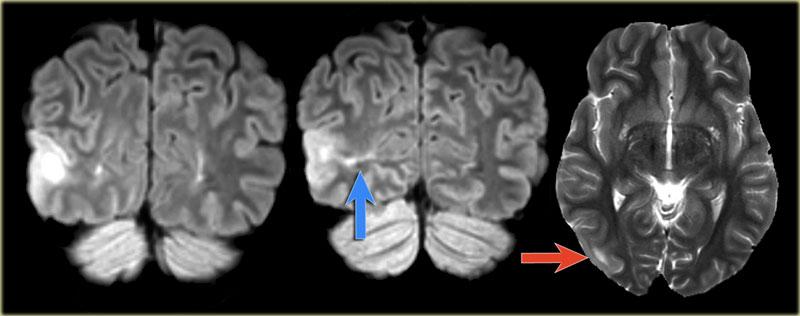

Hình ảnh của bệnh nhân nam 27 tuổi bị động kinh thùy chẩm kháng trị.

Ảnh FLAIR mặt phẳng coronal và T2W mặt phẳng axial cho thấy dày vỏ não tăng tín hiệu T2 và tăng tín hiệu ở vỏ não và vùng dưới vỏ.

Lưu ý vùng tăng tín hiệu dưới vỏ kéo dài đến não thất bên phải, biểu hiện dấu hiệu xuyên vỏ (mũi tên xanh).

Dấu hiệu xuyên vỏ (transmantle sign) ghi nhận ở một bệnh nhân khác bị loạn sản vỏ não khu trú.